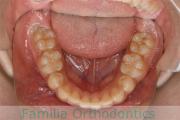

- ≫治療前

上顎

下顎

- ≫治療中 ステップ1

- ≫治療後

出っ歯とかみ合わせを治したいとのことで小学生の時に来院されました。一期治療ではリップバンパーのみで経過を観察し、中学生の時に再診断をしました。やや叢生(でこぼこ、ガタガタ)がきつめでしたが、拡大・非抜歯・マルチブラケット法にて治療を行いました。二期治療は、2年半、30回の通院が必要でした。

非抜歯治療を行いましたので、後戻りのリスクが高めですので、保定観察が重要です。